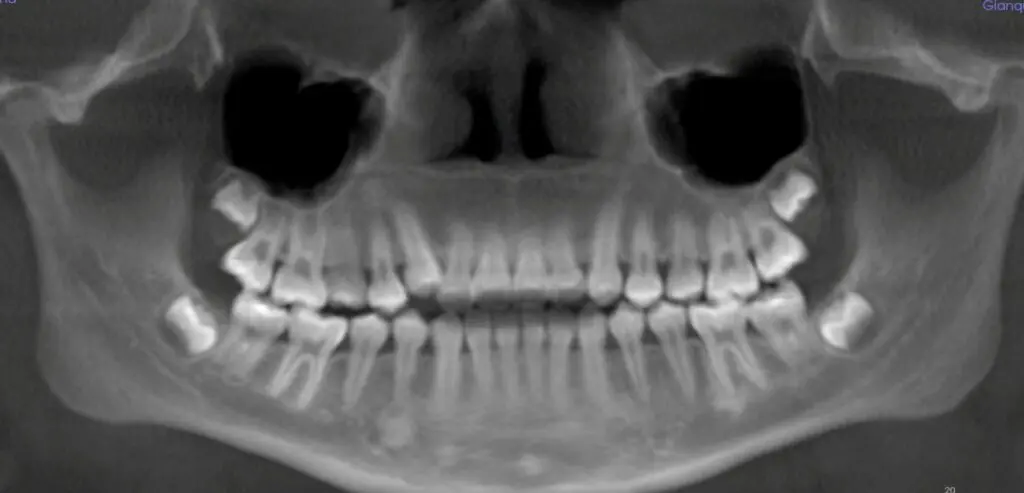

Traditionally, orthodontic diagnosis and treatment planning has been done with 2-dimensional imaging using a panoramic x-ray, generally showing what teeth are present and where they are, and a cephalometric x-ray, which is a side view that gives a general idea of jaw positioning. Cone Beam Computed Tomography, or CBCT, is a 3D x-ray that shows so much more information in a single image, with much higher accuracy than ever before.

Let’s compare the 2D and 3D images in the cases below. You will be able to see the benefits of 3D imaging.

Case 1: Need for extractions. In the 2D x-rays, it looks like there’s plenty of room to fit all of the teeth in the bone. But when looking at the case in 3D, it becomes obvious that the roots of several teeth are already outside the bone, and treating the case without removing teeth would only make this worse.